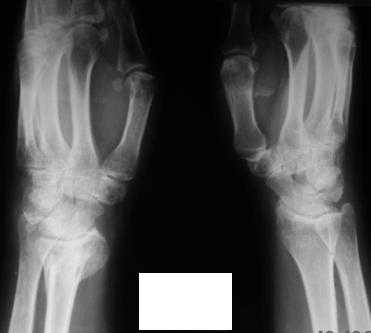

Уважаемые коллеги! Обратилась женщина, 55 лет. Травма 3 месяца назад, лечилась по месту жительства (Рис.1). Косорукость, боли, ограничение движений.

Досняли - рис.2-6. Хотелось-бы услышать мнения об объеме операции. С уважением, Юрий Алексеевич Булахтинглавный травматолог Камчатского Военно-морского госпиталя

u pazientki po nauchnomu ulna abutment/impingment syndrome posle posttraumaticheskogo ukorochenia radiusa

na rengene znachitelnoe ukorochenie radiusa, sustavnaia poverchnost naklonena dorsalno chresmerno , chetko vidno nekongruentnost DRUJ - distalnogo radioulnarnogo sustava ,ulna prosto vtikaetsia v triquetrum .

Да, действительно, в наличии так называемый посттравматический ulnar impaction syndrome. Есть несколько вариантов лечения этой патологии-данного случая. Вполне можно выбрать вариант и предложенной выше тактики. А кто-то даже после остеотомии лучевой кости наложит аппарат внешней фиксации и одновременно устранит дорсальную ангуляцию и удлинит лучевую кость. Можно предусмотреть и другие варианты. Если не очень расстраивает дорсальная ангуляция, то при отсутствии артроза в области дистального радиоульнарного сочленения ( а пока такого, по-видимому, нет)и нестабильности этого сустава можно просто укоротить локтевую кость. Причем возможно сделать поперечную остеотомию ( если есть ладонный или тыльный подвывих головки локтевой кости, то можно сделать еще и клиновидную остеотомию по ладони или по тылу), либо выполнить косую остеотомию ( при подвывихе головки даже клин в этом случае не надо делать). Если есть артроз, нестабильность, то нужно рассматривать другие варианты - Дарраха в модификациях, Сауве-Капанджи, артропластику(?).